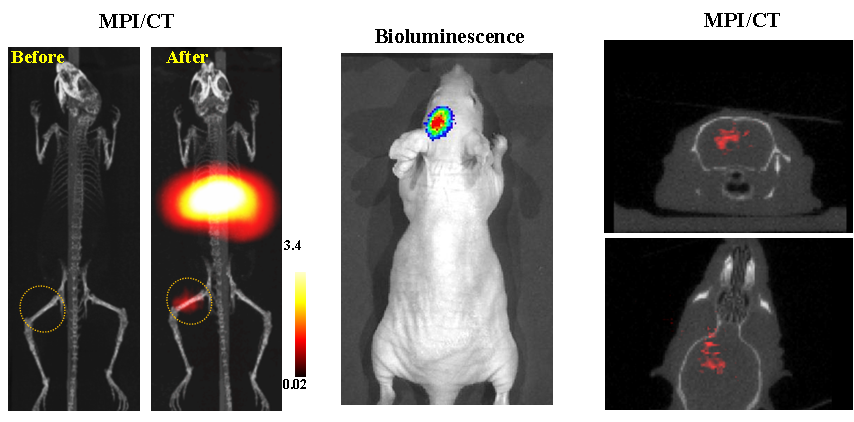

今年二月份,宋国胜教授与斯坦福大学饶江宏教授合作,通过系统的研究获得了影响磁性粒子成像信号的作用规律和关键原理,开发了新型磁性粒子探针---FeCo合金粒子,并首次应用于磁性粒子成像(MPI)。该造影剂在极低含量时(5 ng)仍具有很强的造影效果。这意味着,未来在进行人体成像时,可以使用更小剂量的造影剂,从而避免高剂量造影剂引起的肾肝损伤。基于MPI的直接成像原理,我们可以对造影剂进行正相和无背景干扰的活体成像,极大地提高信噪比。这项技术为肿瘤早期诊断、癌细胞示踪、脑中风、药物输送治疗、肺部灌注成像、胃肠出血、神经退行性疾病、磁热治疗等在活体中的可视化研究,提供了强有力的手段。相关研究成果以成人漫画

为第一单位发表在Nature 子刊《Nature Biomedical Engineering》。该期刊是“生物医学工程”的顶级期刊。宋国胜教授为该论文的共同通讯作者。